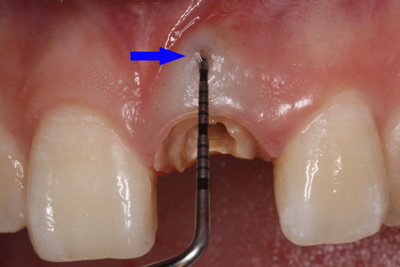

患者外院螺紋樁核加樹脂冠

X線片顯示螺紋釘出根管壁

唇側(cè)出現(xiàn)瘺管